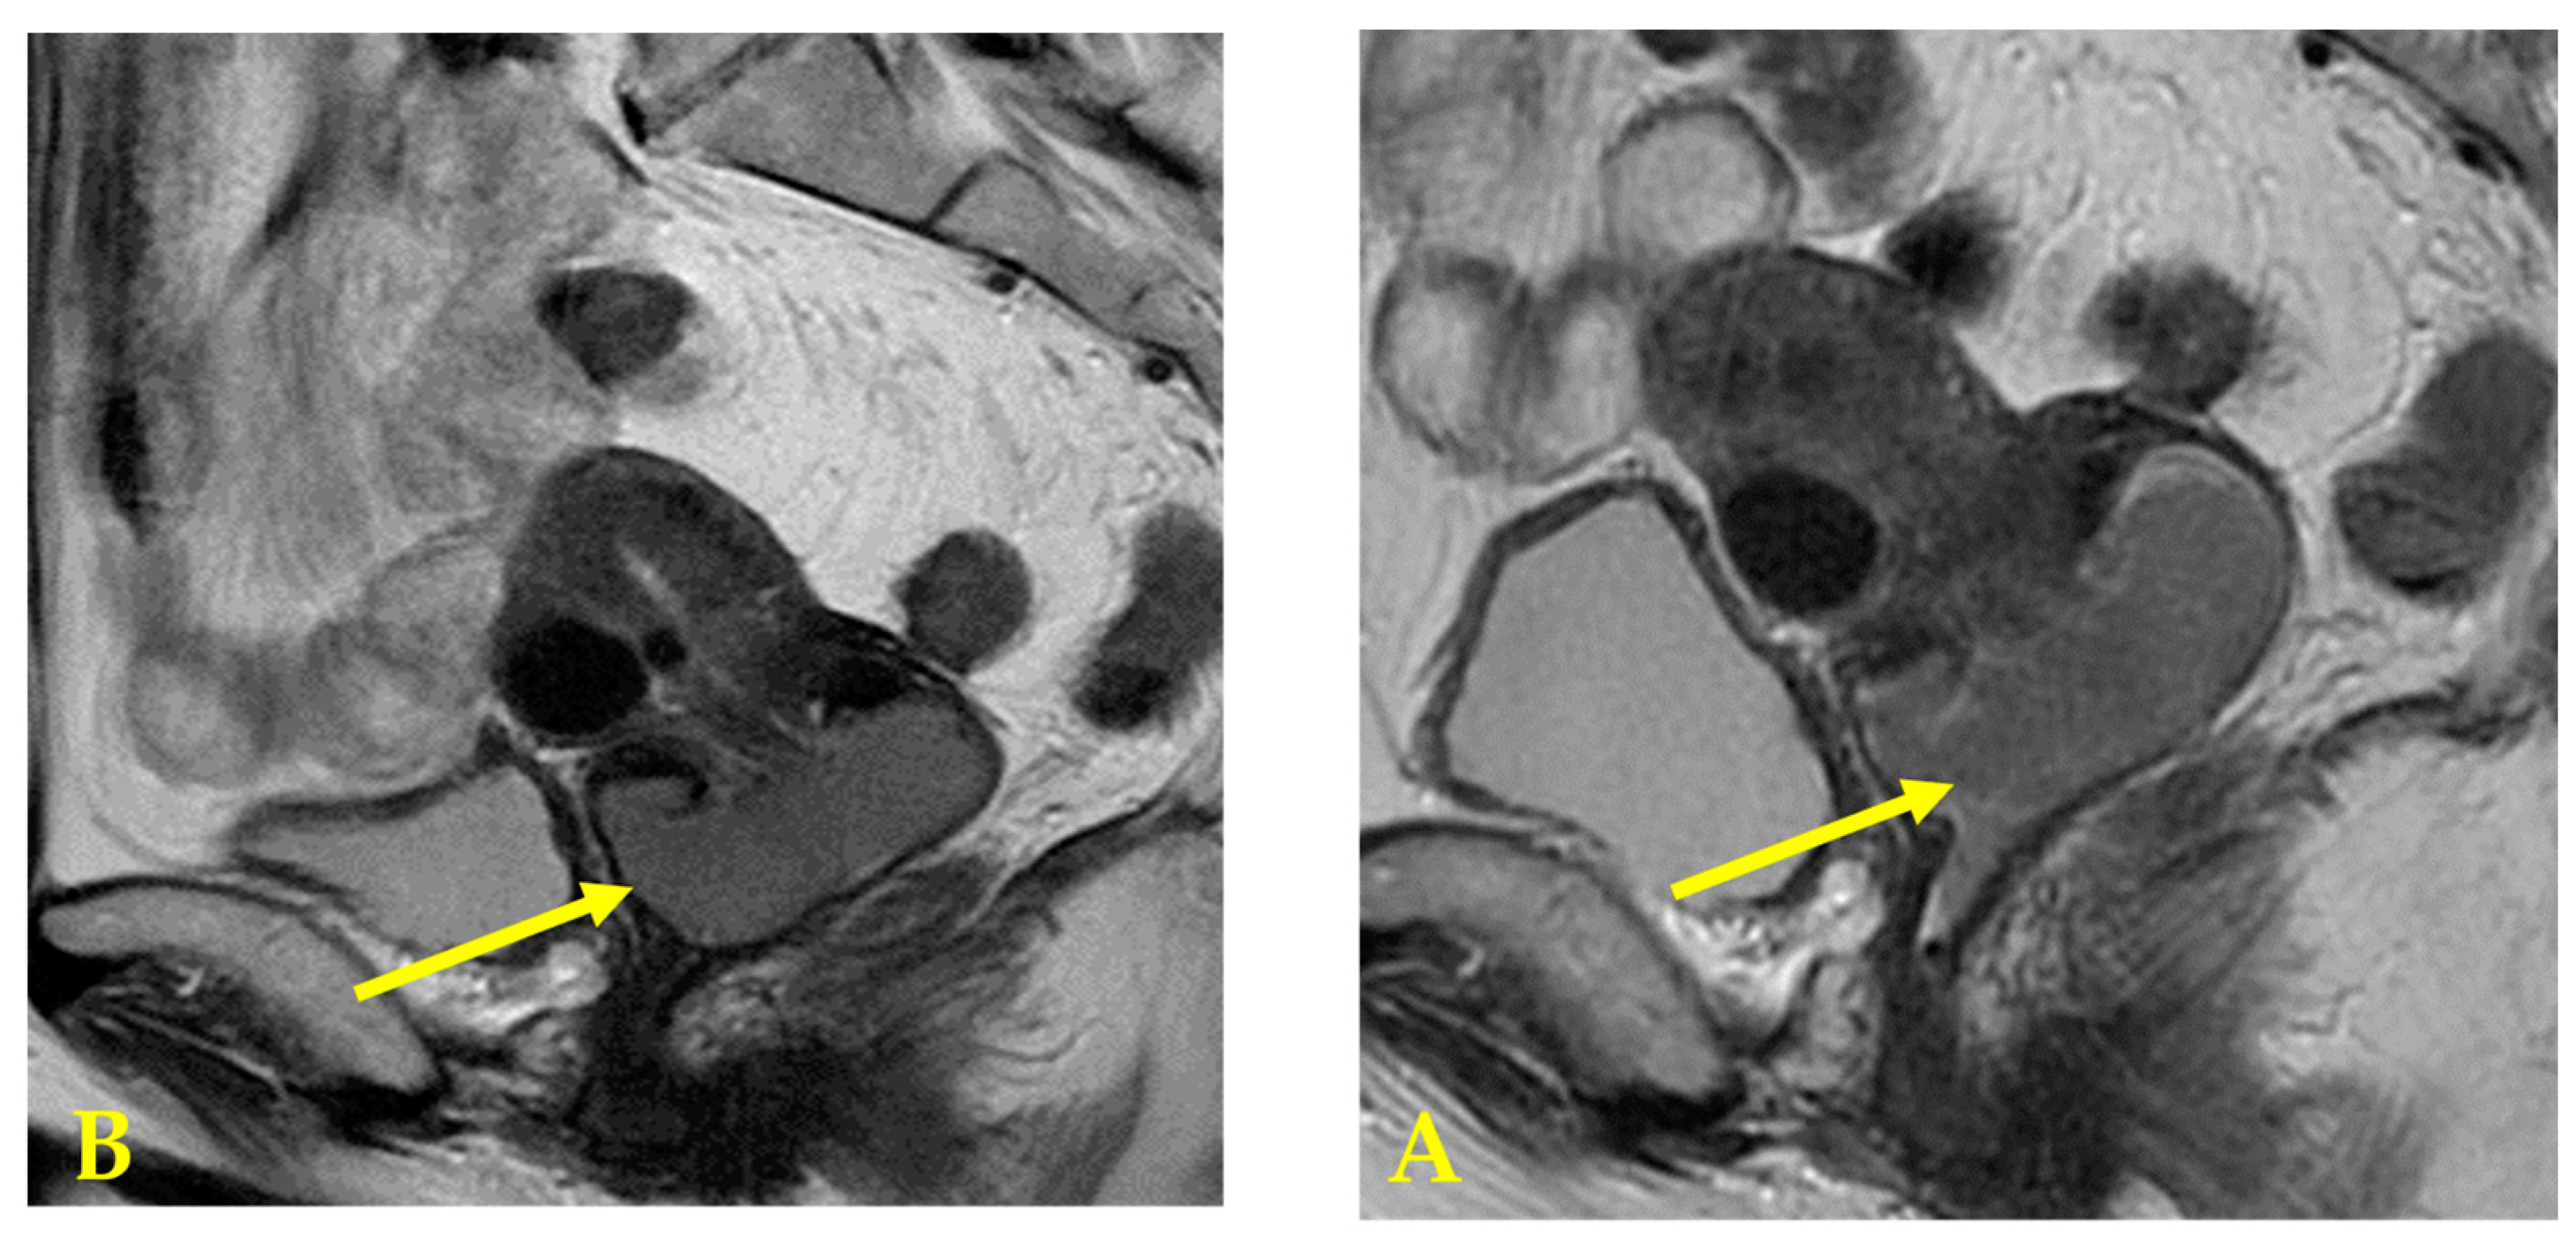

Figure 3.

(A) Pelvic MRI T2 weighted image: A cervical tumor measuring 53 × 26 mm. Before chemotherapy. (B) Pelvic MRI T2 weighted image: After one course of neoadjuvant chemotherapy with paclitaxel–carboplatin (PC). A cervical tumor measuring 43 × 23 mm. The tumor shrank and PR was diagnosed.